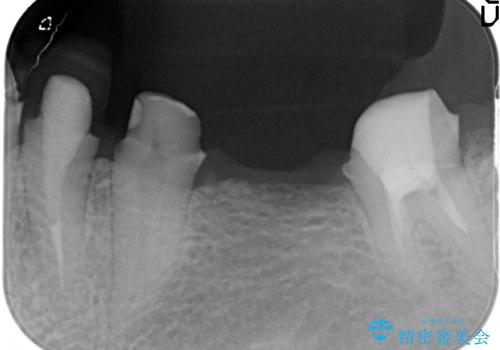

- 毎回食事のたびに食べかすがつまり、見た目も気になる銀歯のブリッジやりかえを希望され来院されました。

精度の高いジルコニアブリッジの製作に加え歯茎にぴったりとそわせたオベイトポンティック形態とすることで清掃性・審美性に優れたブリッジを製作します。